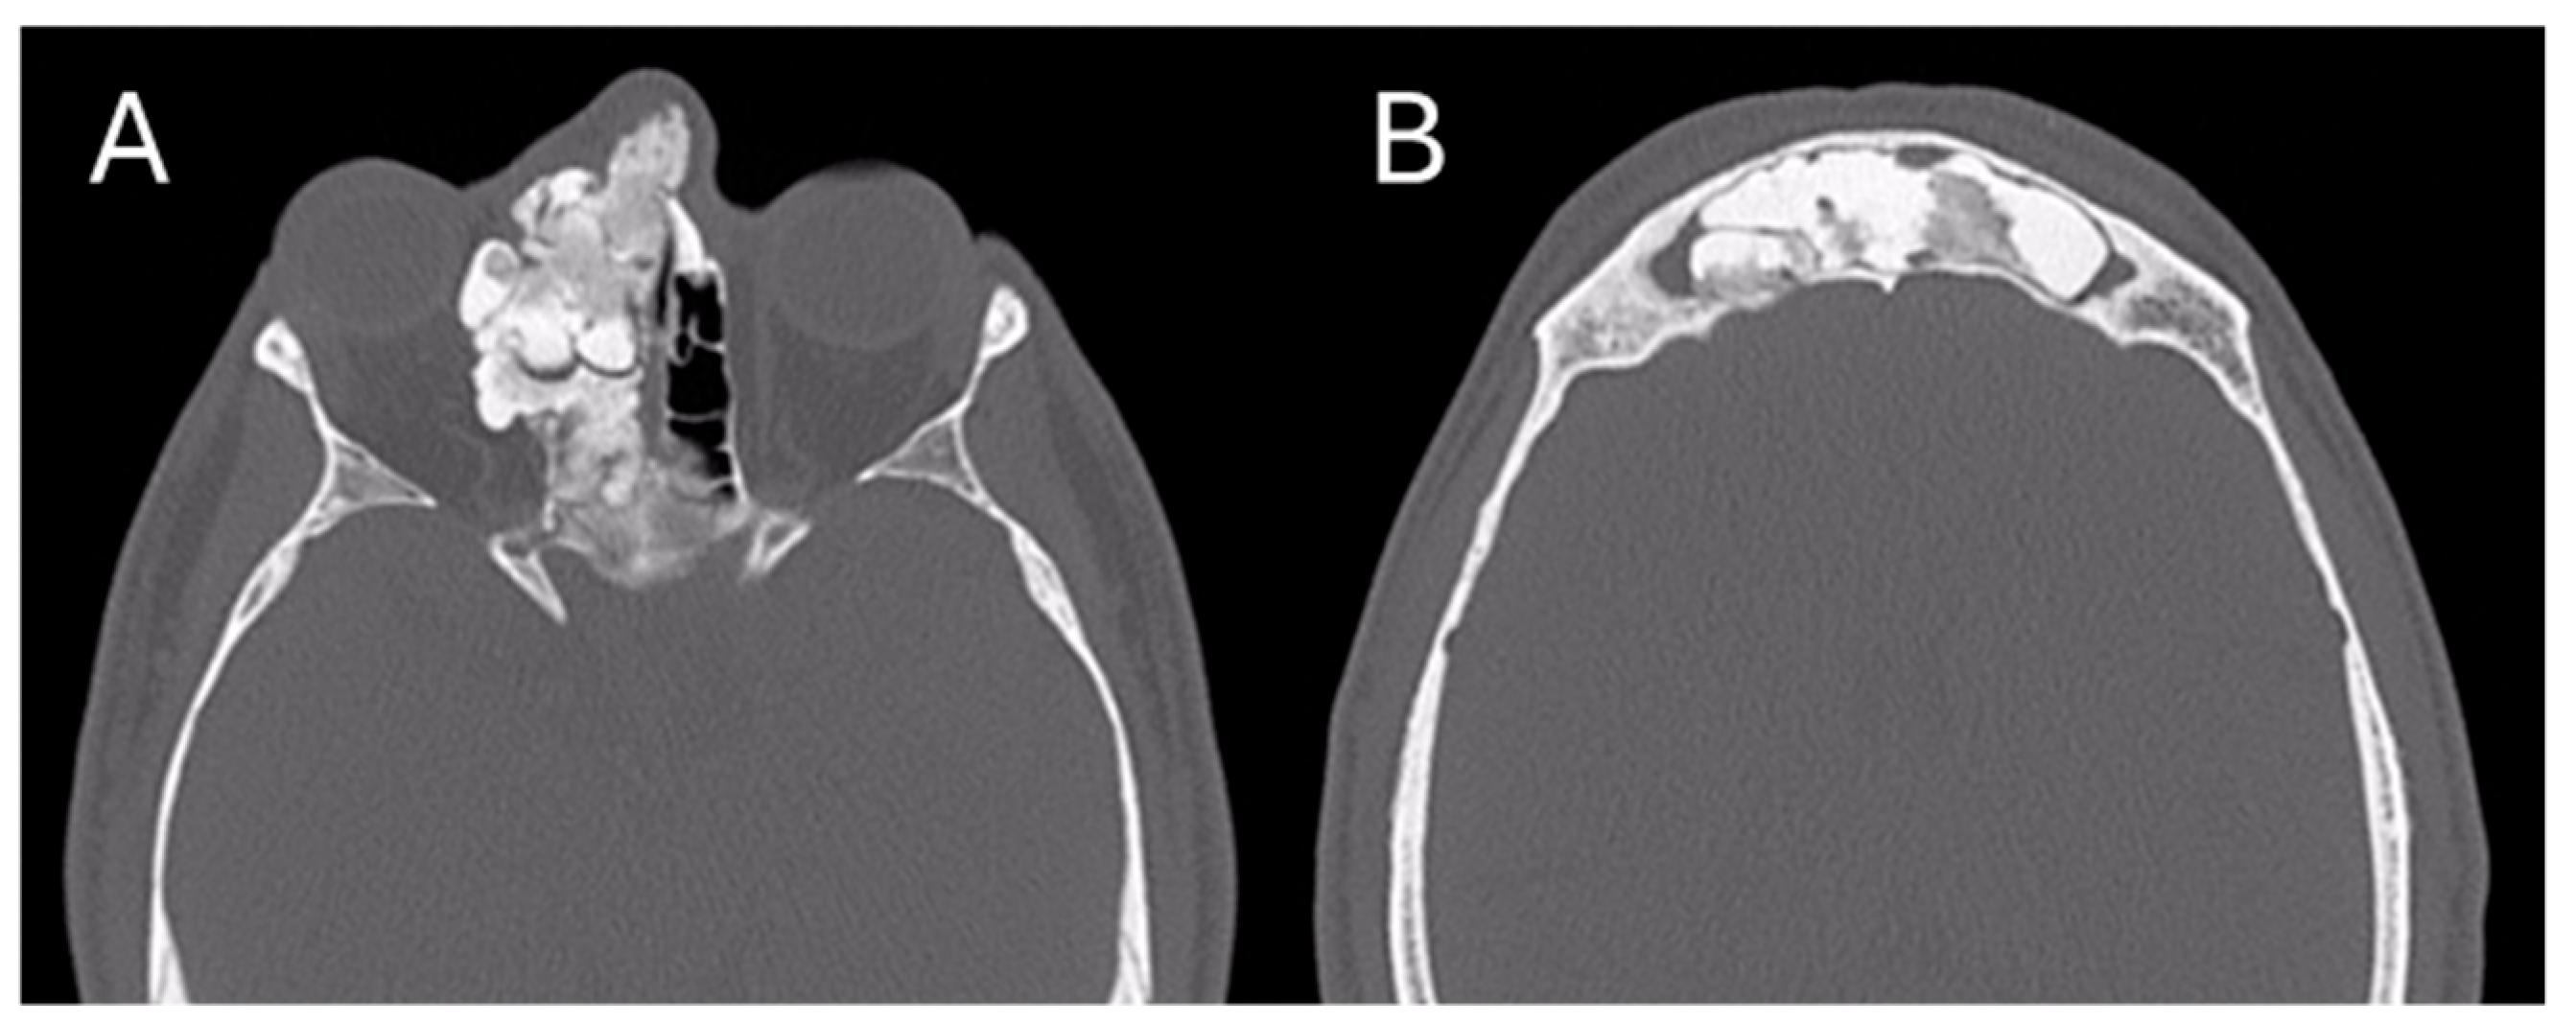

In July 2023, a 35-year-old man came to the attention of the Maxillofacial Surgery Unit of Azienda Ospedaliera Universitaria Senese of Siena to evaluate a facial asymmetry that worsened over the years. On physical examination, the eurythmy of the face was not preserved with marked exophthalmos and a dystopia of the right eye; the patient reported no sensory nerve abnormalities nor olfactory or visual deficits. The patient also reported a history of sinusitis. The skull CT scan was already performed, and it showed a large calcific-fibrotic-mixed component neoformation centered in the body of the ethmoid, extending caudally towards the right nasal fossa and cranially towards the frontal sinus occupying it bilaterally. Posteriorly, the lesion extended towards the sphenoid projecting into the anterior cranial fossa, anteriorly, and laterally towards the right orbit (Figure 4).

Figure 4. Pre-operative CT image of Patient 2. Two axial cuts are appreciated (A) The lesion localized at the ethmoidal level (B) The lesion localizedin the right frontal sinus.